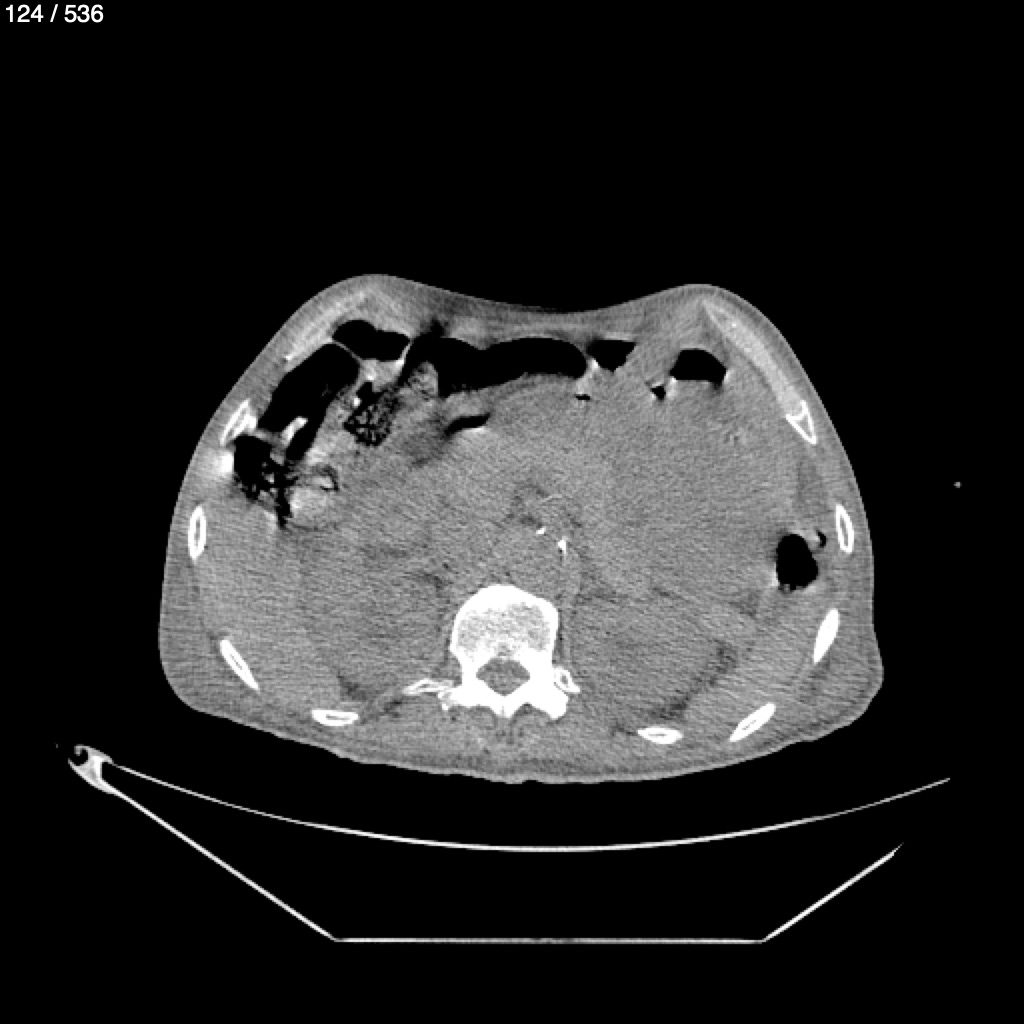

Angel Villalobos Palomeque 73 A - T.C Abdomen Simple